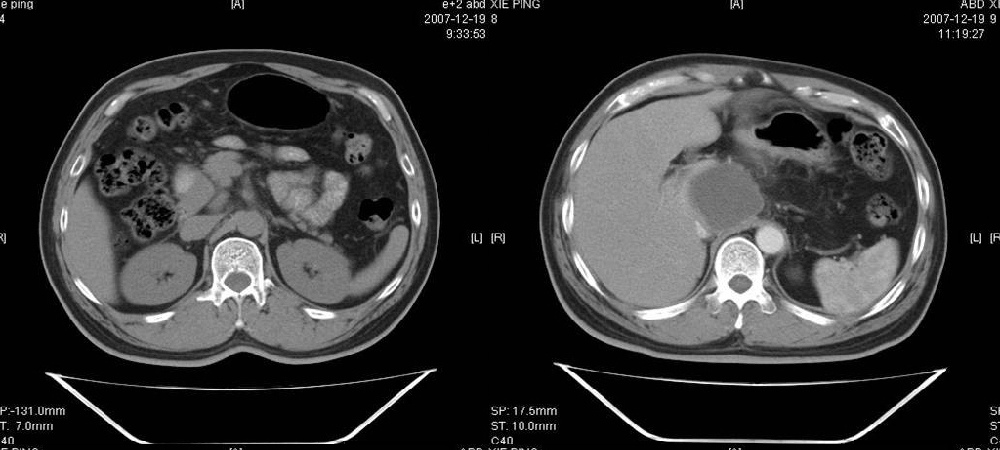

临床病史:患者,男,53岁,因反复上腹部饱胀不适2+月,在餐后或饥饿时明显,伴呃逆,无呕吐、呕血,无腹痛腹泻;2年前腹腔镜胆囊切除,否认肝炎、结核等病史。

胰腺头部低密度囊性病灶,边缘清楚,增强后囊壁略强化。考虑:胰头假性囊肿!

胰腺头部(或肝脏尾叶部)低密度囊性病灶,边缘清楚,增强后囊壁略强化。考虑:胰头假性囊肿. 或肝脏尾叶部囊肿。

pmrc显示病变与12指肠关系密切,与胆系不相通。

餐后或饥饿时明显,考虑12指肠溃疡并穿孔形成假囊肿(外瘘积液包裹),与lc手术无关。

考虑十二指肠憩室。从影像上看,病变位于下腔静脉前胰头后方十二指肠内侧,肝尾叶受压,说明病变来源于后腹膜;胰胆管成像胰管和胆道未见扩张,总胆管中段受压未显示,上下段正常,所以不考虑来源与于肝尾叶和总胆管的囊肿。考虑为十二指肠憩室或小网膜囊肿。

楼上高手,本例的确是一例十二指肠憩室.